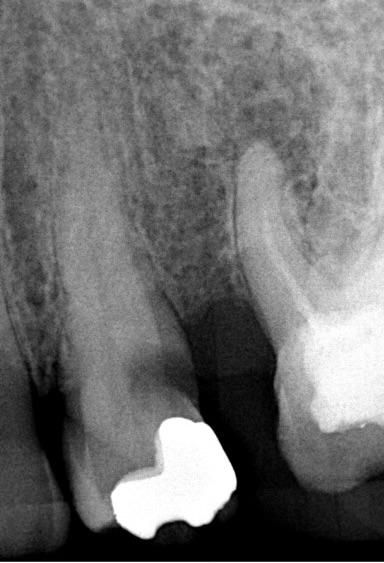

In endodontics, every case reminds us that anatomy can be wonderfully unpredictable. This particular premolar presented with a molar-like multi-canal morphology, complete with extensive coronal caries. The case beautifully highlights the critical importance of accurate diagnosis, thorough caries removal, and a precisely designed access preparation.

Premolar presenting with an aberrant molar-like multi-canal morphology and extensive coronal caries, requiring meticulous access preparation and maximum structural preservation.